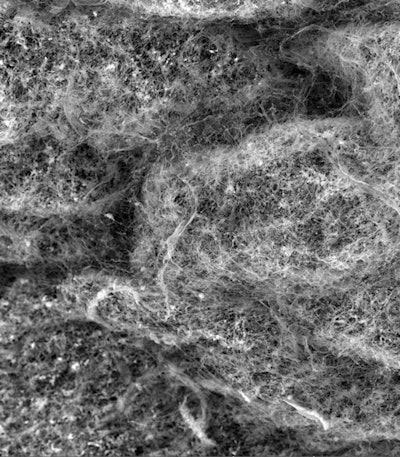

Two overlayed fluorescent microscopy images of S. mutans, the primary bacteria responsible for dental cavities. When S. mutans forms biofilms on the tooth surface, it produces organic acids as metabolic byproducts that dissolve tooth enamel. The green fluorescent image shows S. mutans biofilm mass when grown in the presence of sucrose, a substrate necessary for substantial bacterial attachment and biofilm formation. The red fluorescent image overlayed depicts S. mutans biofilm mass in the presence of sucrose and purified human salivary mucins. Mucins are key structural components of mucus and saliva that play an important role in host defense. Image courtesy of Nicole Kavanaugh of MIT and the American Society for Microbiology.